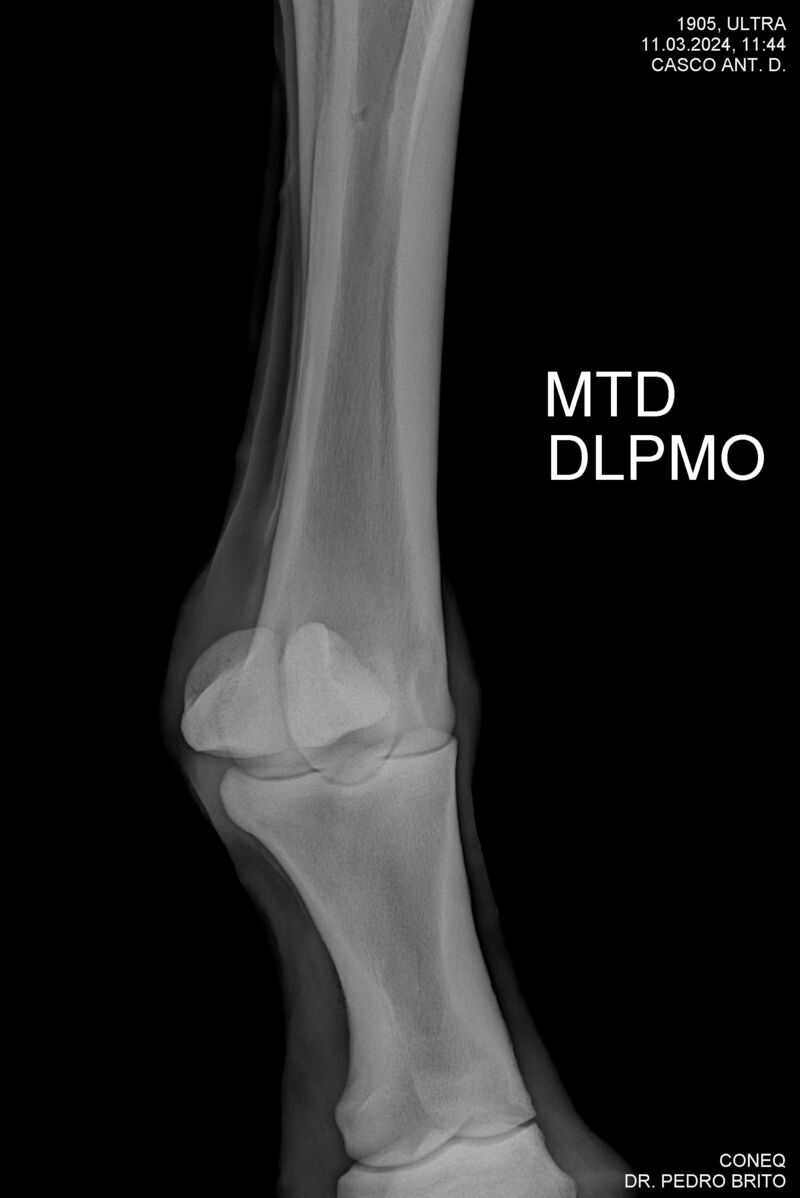

ULTRA DO CACH

Raça: BRASILEIRO DE HIPISMO

Sexo: CASTRADO - CASTRADO

Nascimento: 22/11/2020

Altura Aproximada: 1,67

Pel.: CASTANHO

Registro: 25966-BH

Vend.: HARAS CACHOEIRINHA

Local : PIRASSUNUNGA/SP